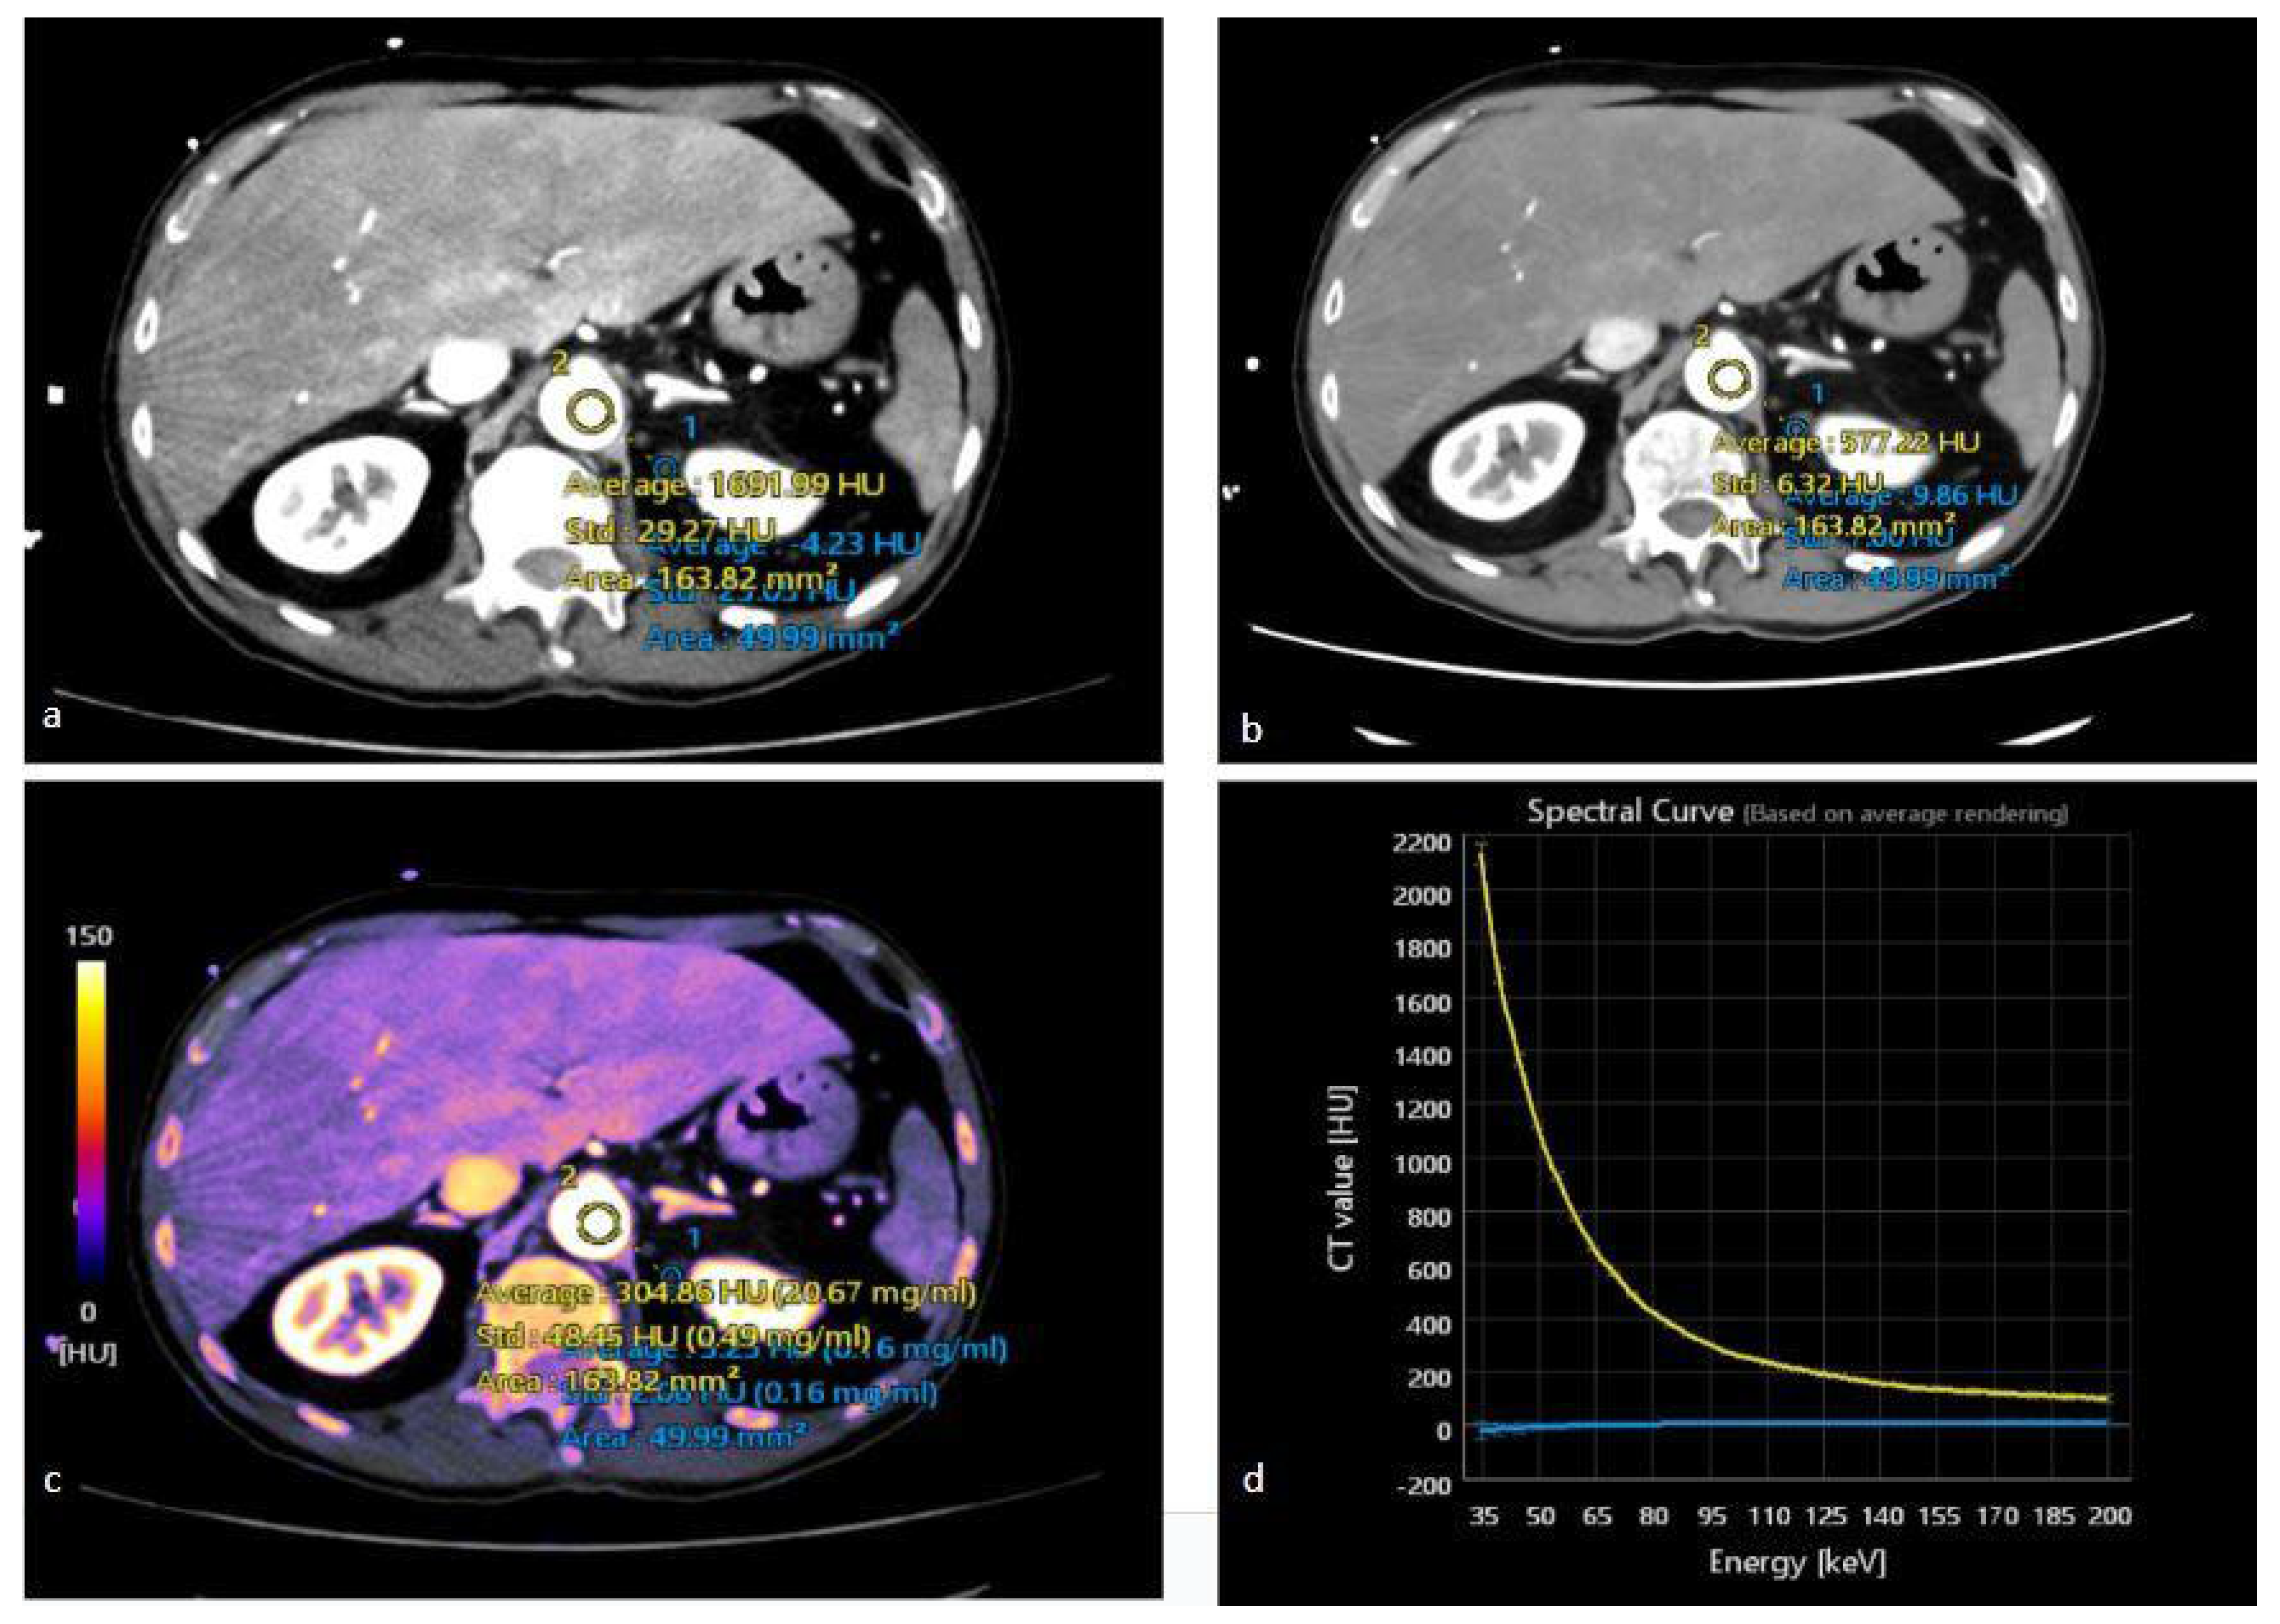

3.3. Iodine Maps

3.4. Spectral HU Curves

- Marcon, J.; Graser, A.; Horst, D.; Casuscelli, J.; Spek, A.; Stief, C.G.; Reiser, M.F.; Rübenthaler, J.; Buchner, A.; Staehler, M. Papillary vs Clear Cell Renal Cell Carcinoma. Differentiation and Grading by Iodine Concentration Using DECT-Correlation with Microvascular Density. Eur. Radiol. 2020, 30, 1–10. [Google Scholar] [CrossRef] [PubMed]

- Moleesaide, A.; Maneegarn, A.; Kaewlai, R.; Thiravit, S. Virtual Monochromatic Spectral Attenuation Curve Analysis for Evaluation of Incidentally Detected Small Renal Lesions Using Rapid Kilovoltage-Switching Dual-Energy Computed Tomography. Abdom. Radiol. 2022, 47, 3817–3827. [Google Scholar] [CrossRef]

- Wei, J.; Zhao, J.; Zhang, X.; Wang, D.; Zhang, W.; Wang, Z.; Zhou, J. Analysis of Dual Energy Spectral CT and Pathological Grading of Clear Cell Renal Cell Carcinoma (CcRCC). PLoS ONE 2018, 13, e0195699. [Google Scholar] [CrossRef]

| Wei et al. [64] | Clear cell RCC (ccRCC) | 62 | Histopathology | Cortex phase (CP) and parenchymal phase (PP) | -In the qualitative analysis of the imaging features observed during the combined CP and PP, sensitivity and specificity of 80% and 77.8%, respectively, were achieved for differentiating between low- and high-grade ccRCC. -The quantitative parameters analysis with CT spectral imaging compared with qualitative CT image analysis improved the sensitivity from 80% to 90.3% and the specificity from 77.8% to 87.5%. |

| Marcon et al. [56] | Clear-cell RCC and papillary RCC | 53 patients with clear-cell RCC (ccRCC) and 15 with papillary RCC (pRCC) | Histopathology | Nephrographic phase DECT | -Analysis of iodine concentration (IC) showed a significant difference between pRCC and ccRCC (p < 0.001). -Mean IC for ccRCC was 4.83 ± 1.75 mg/mL (range 2.2–11.5 mg/mL); for pRCC, it was 2.53 ± 1.59 (range 0.4–6.6 mg/mL). -ROC analysis revealed an ideal cutoff value of ≤3.1 mg/mL (AUC 0.866, p < 0.001) regarding the distinction between pRCCs and ccRCCs. -The calculated specificity was 90.6%, with a sensitivity of 73.3% and an accuracy of 86.8%. |